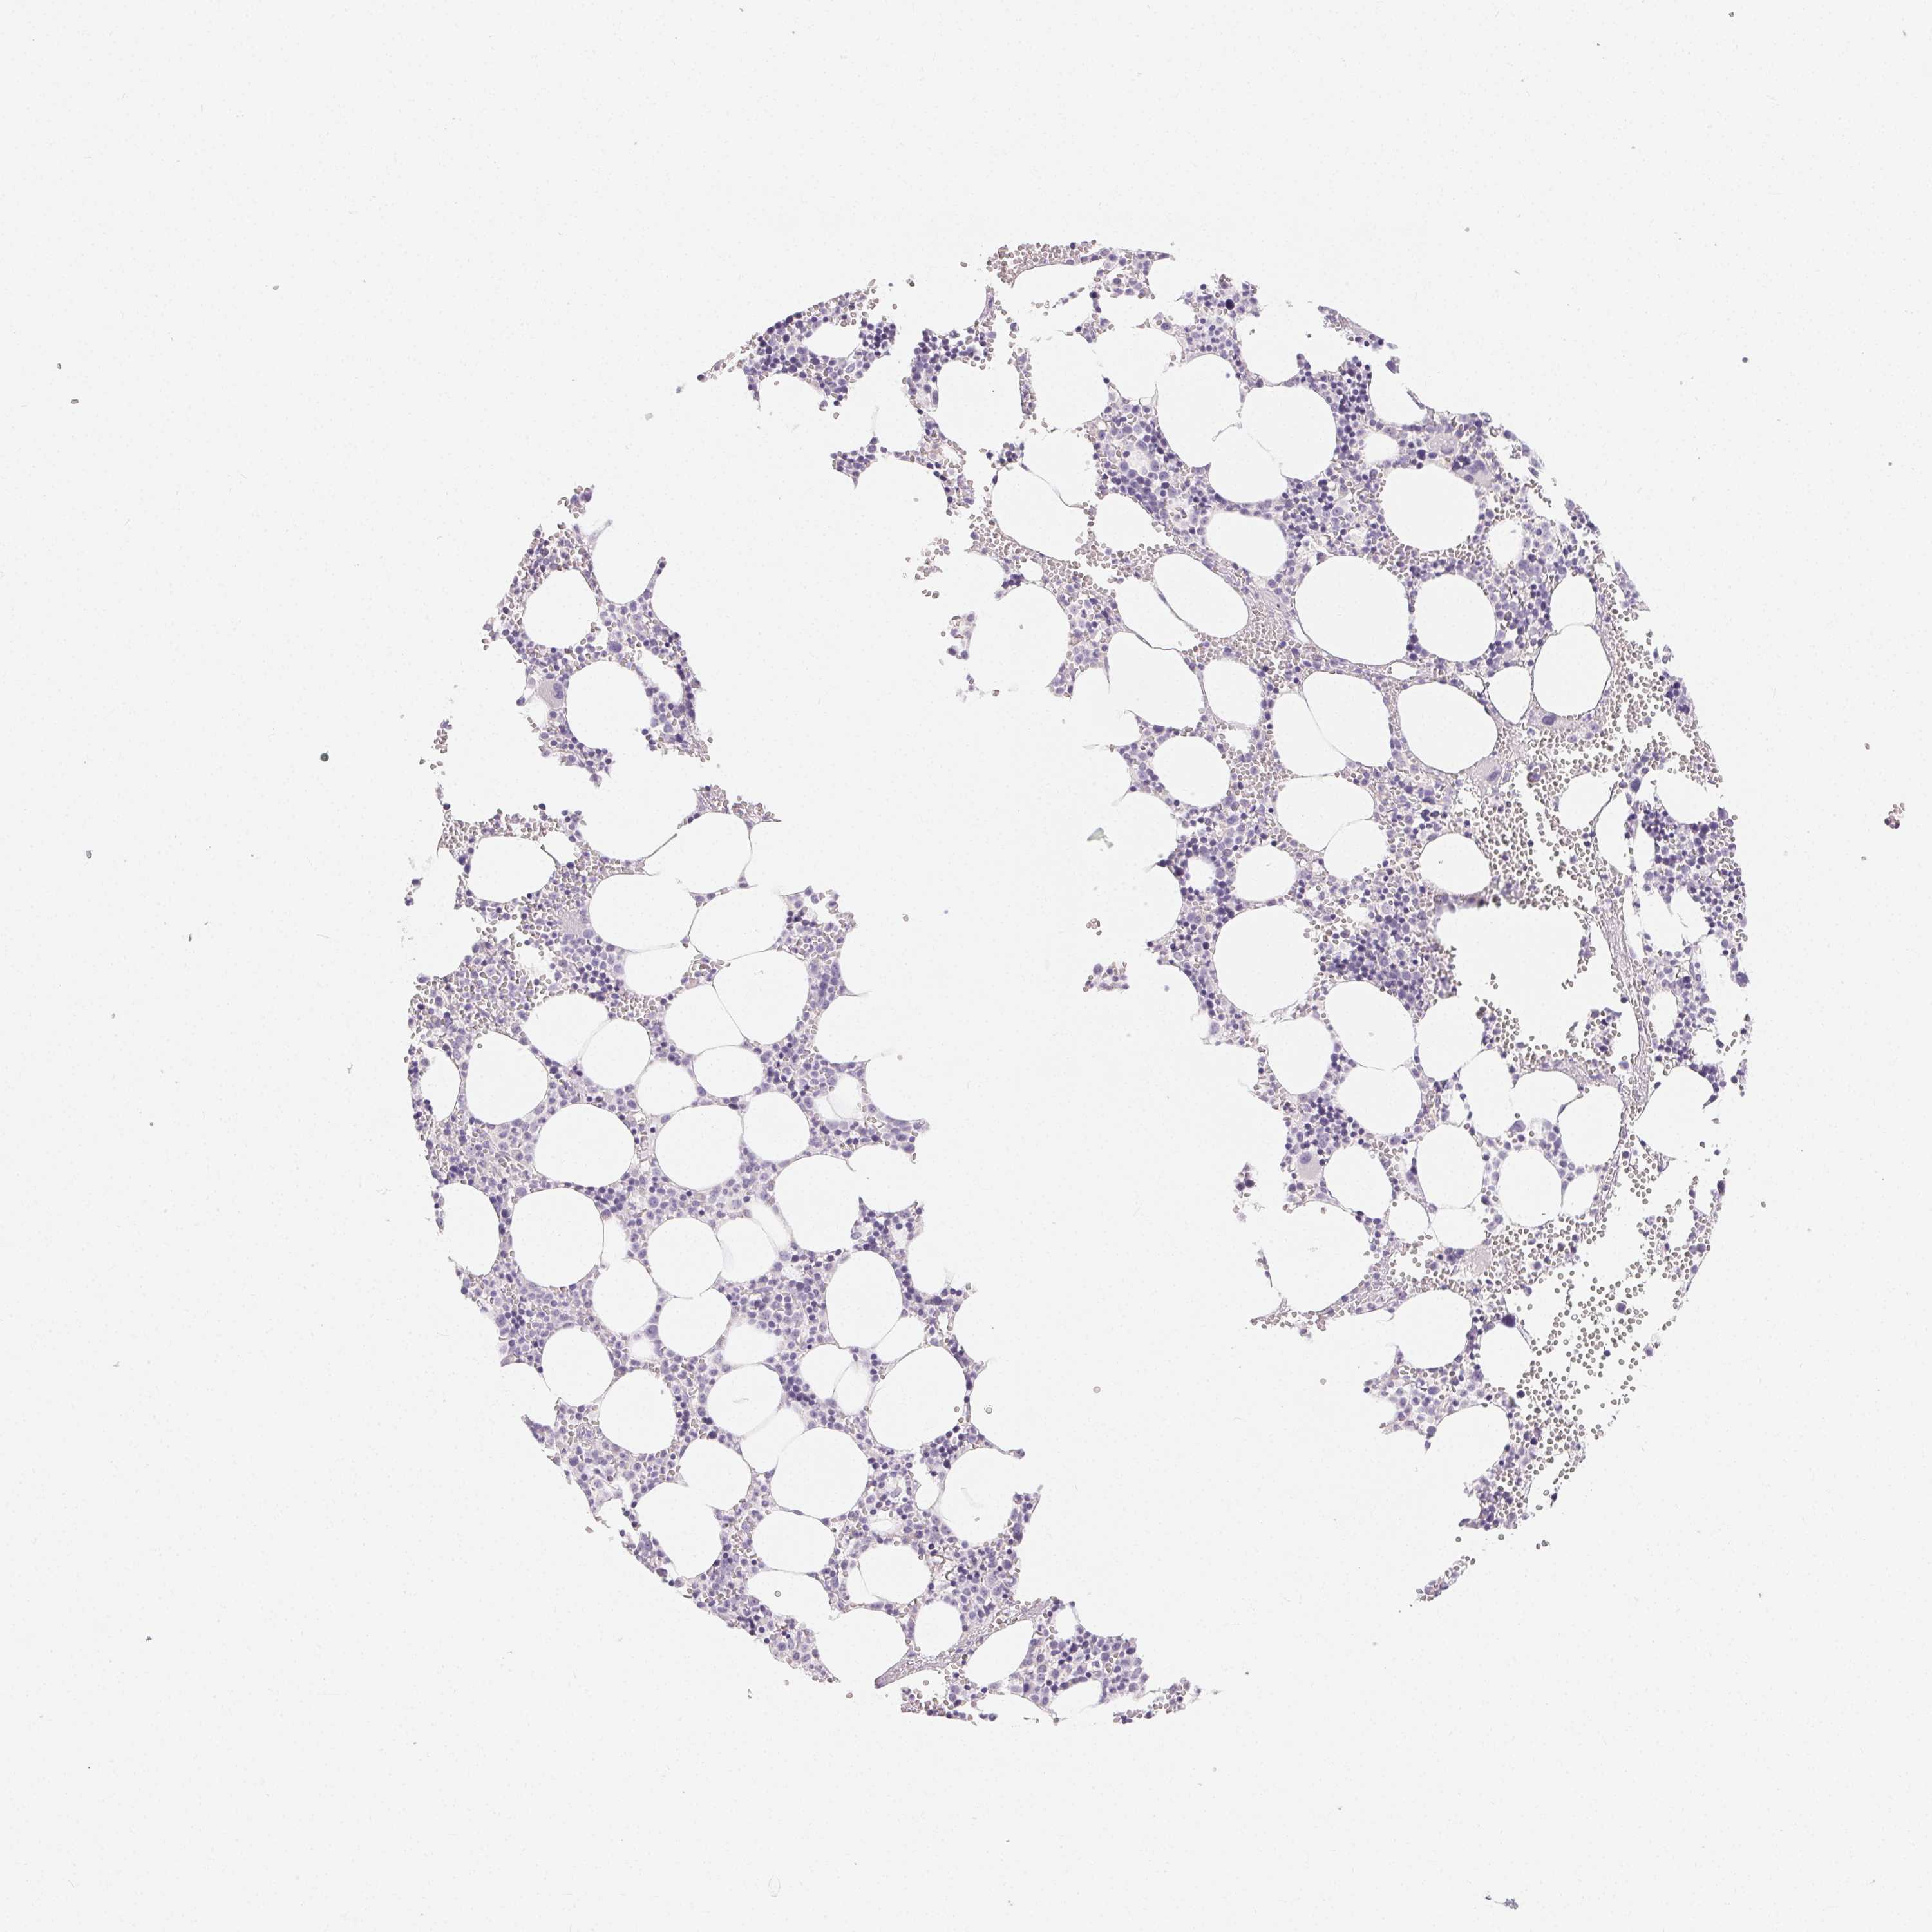

TISSUE PRIMARY DATA BONE MARROW Show tissue menu

BONE MARROW - Antibody stainingi

Antibody staining in the annotated cell types in the current human tissue is reported as not detected, low, medium, or high, based on conventional immunohistochemistry profiling in selected tissues. This score is based on the combination of the staining intensity and fraction of stained cells.

Each image is clickable and will lead to virtual microscopy that enables deeper exploration of all samples and also displays staining intensity scores, fraction scores and subcellular localization as well as patient and tissue information for each sample.

Antibody HPA039451Antibody HPA039562

Hematopoietic cells Not detectedNot detected